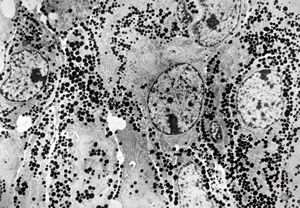

M, 62y. | pheochromocytoma